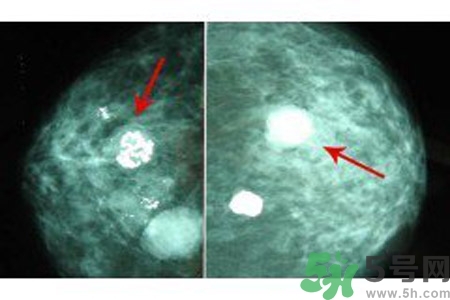

乳腺鈣化點是指可以在乳房造影片上看到鈣沉積物。乳房鈣化點有兩種類型:大鈣化作用和微鈣化作用。

微鈣化作用是可能在迅速分解細胞的部位找到的鈣斑點。這些由迅速分解細胞留下的殘余物可以顯示為微鈣化作用。當(dāng)它們成群大量出現(xiàn)時,即表示有小腫瘤的可能。

乳腺鈣化是指可以在乳房造影看到鈣沉淀物,有多種因素可導(dǎo)致乳腺鈣化,如組織退變、壞死鈣鹽沉積,某些腫瘤分泌含鈣鹽的物質(zhì),使血管周圍組織鈣化。分析鈣化的形態(tài)、數(shù)目、部位以及與周圍結(jié)構(gòu)的關(guān)系,對辨別病變的性質(zhì)有較大的幫助。